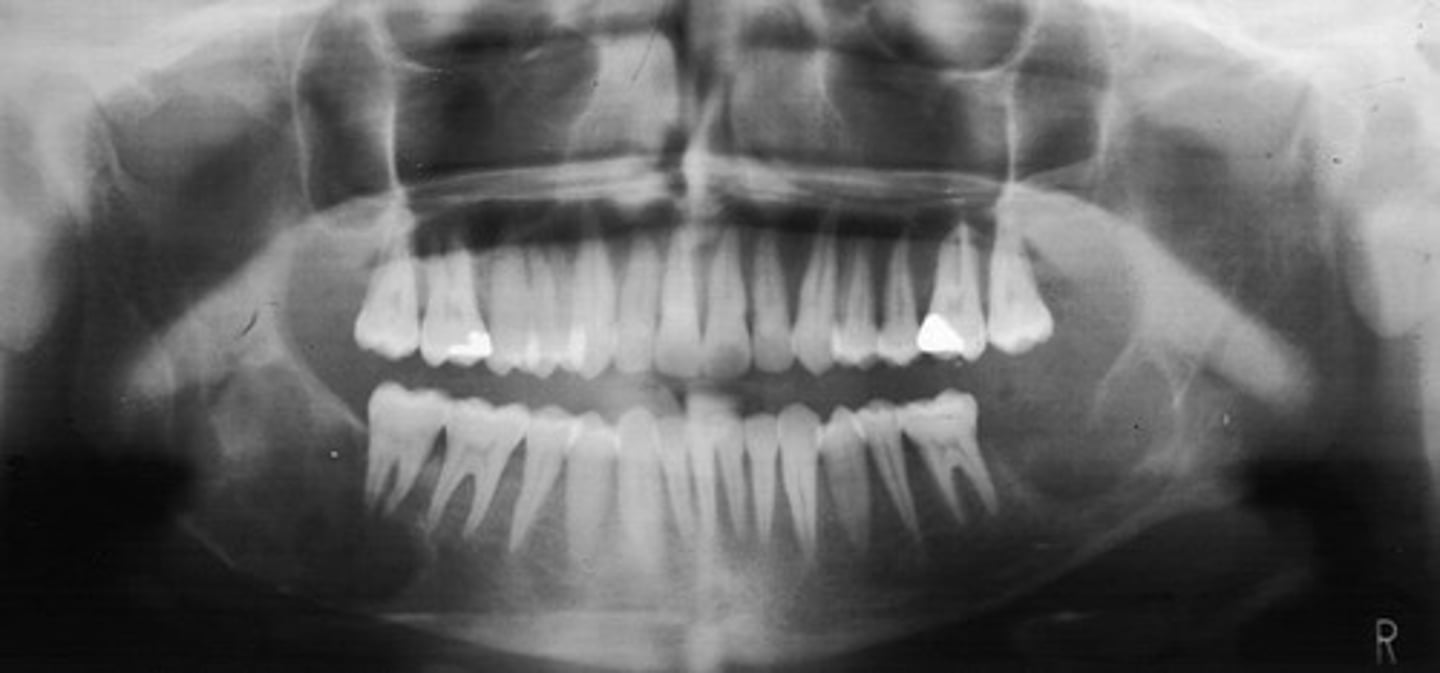

how would you describe this lesion?

A. well-defined, periapical radiolucent lesion associated with #24 and 25

B. ill-defined, periapical radiolucent lesion associated with #24 and 25

C. well- defined, multilocular periapical lesion associated with tooth number 24 and 25

D. mixed density, periapical lesion associated with teeth number 24 and 25

- Also note loss of apical lamina dura of 24, 25

What category would this lesion be part of?

Dysplasia

What would be a differential diagnosis for this lesion?

PCOD (stage 1)

How would you describe the following lesion?

Multiple mixed density periapical target-like entities

The teeth are vital. What category would you put this lesion into?

dysplasia (PCOD)

what could be a differential diagnosis for this lesion?

A. radicular cyst

B. periapical granuloma

C. PCOD (stages 2/3)

D. apical rarefying osteitis